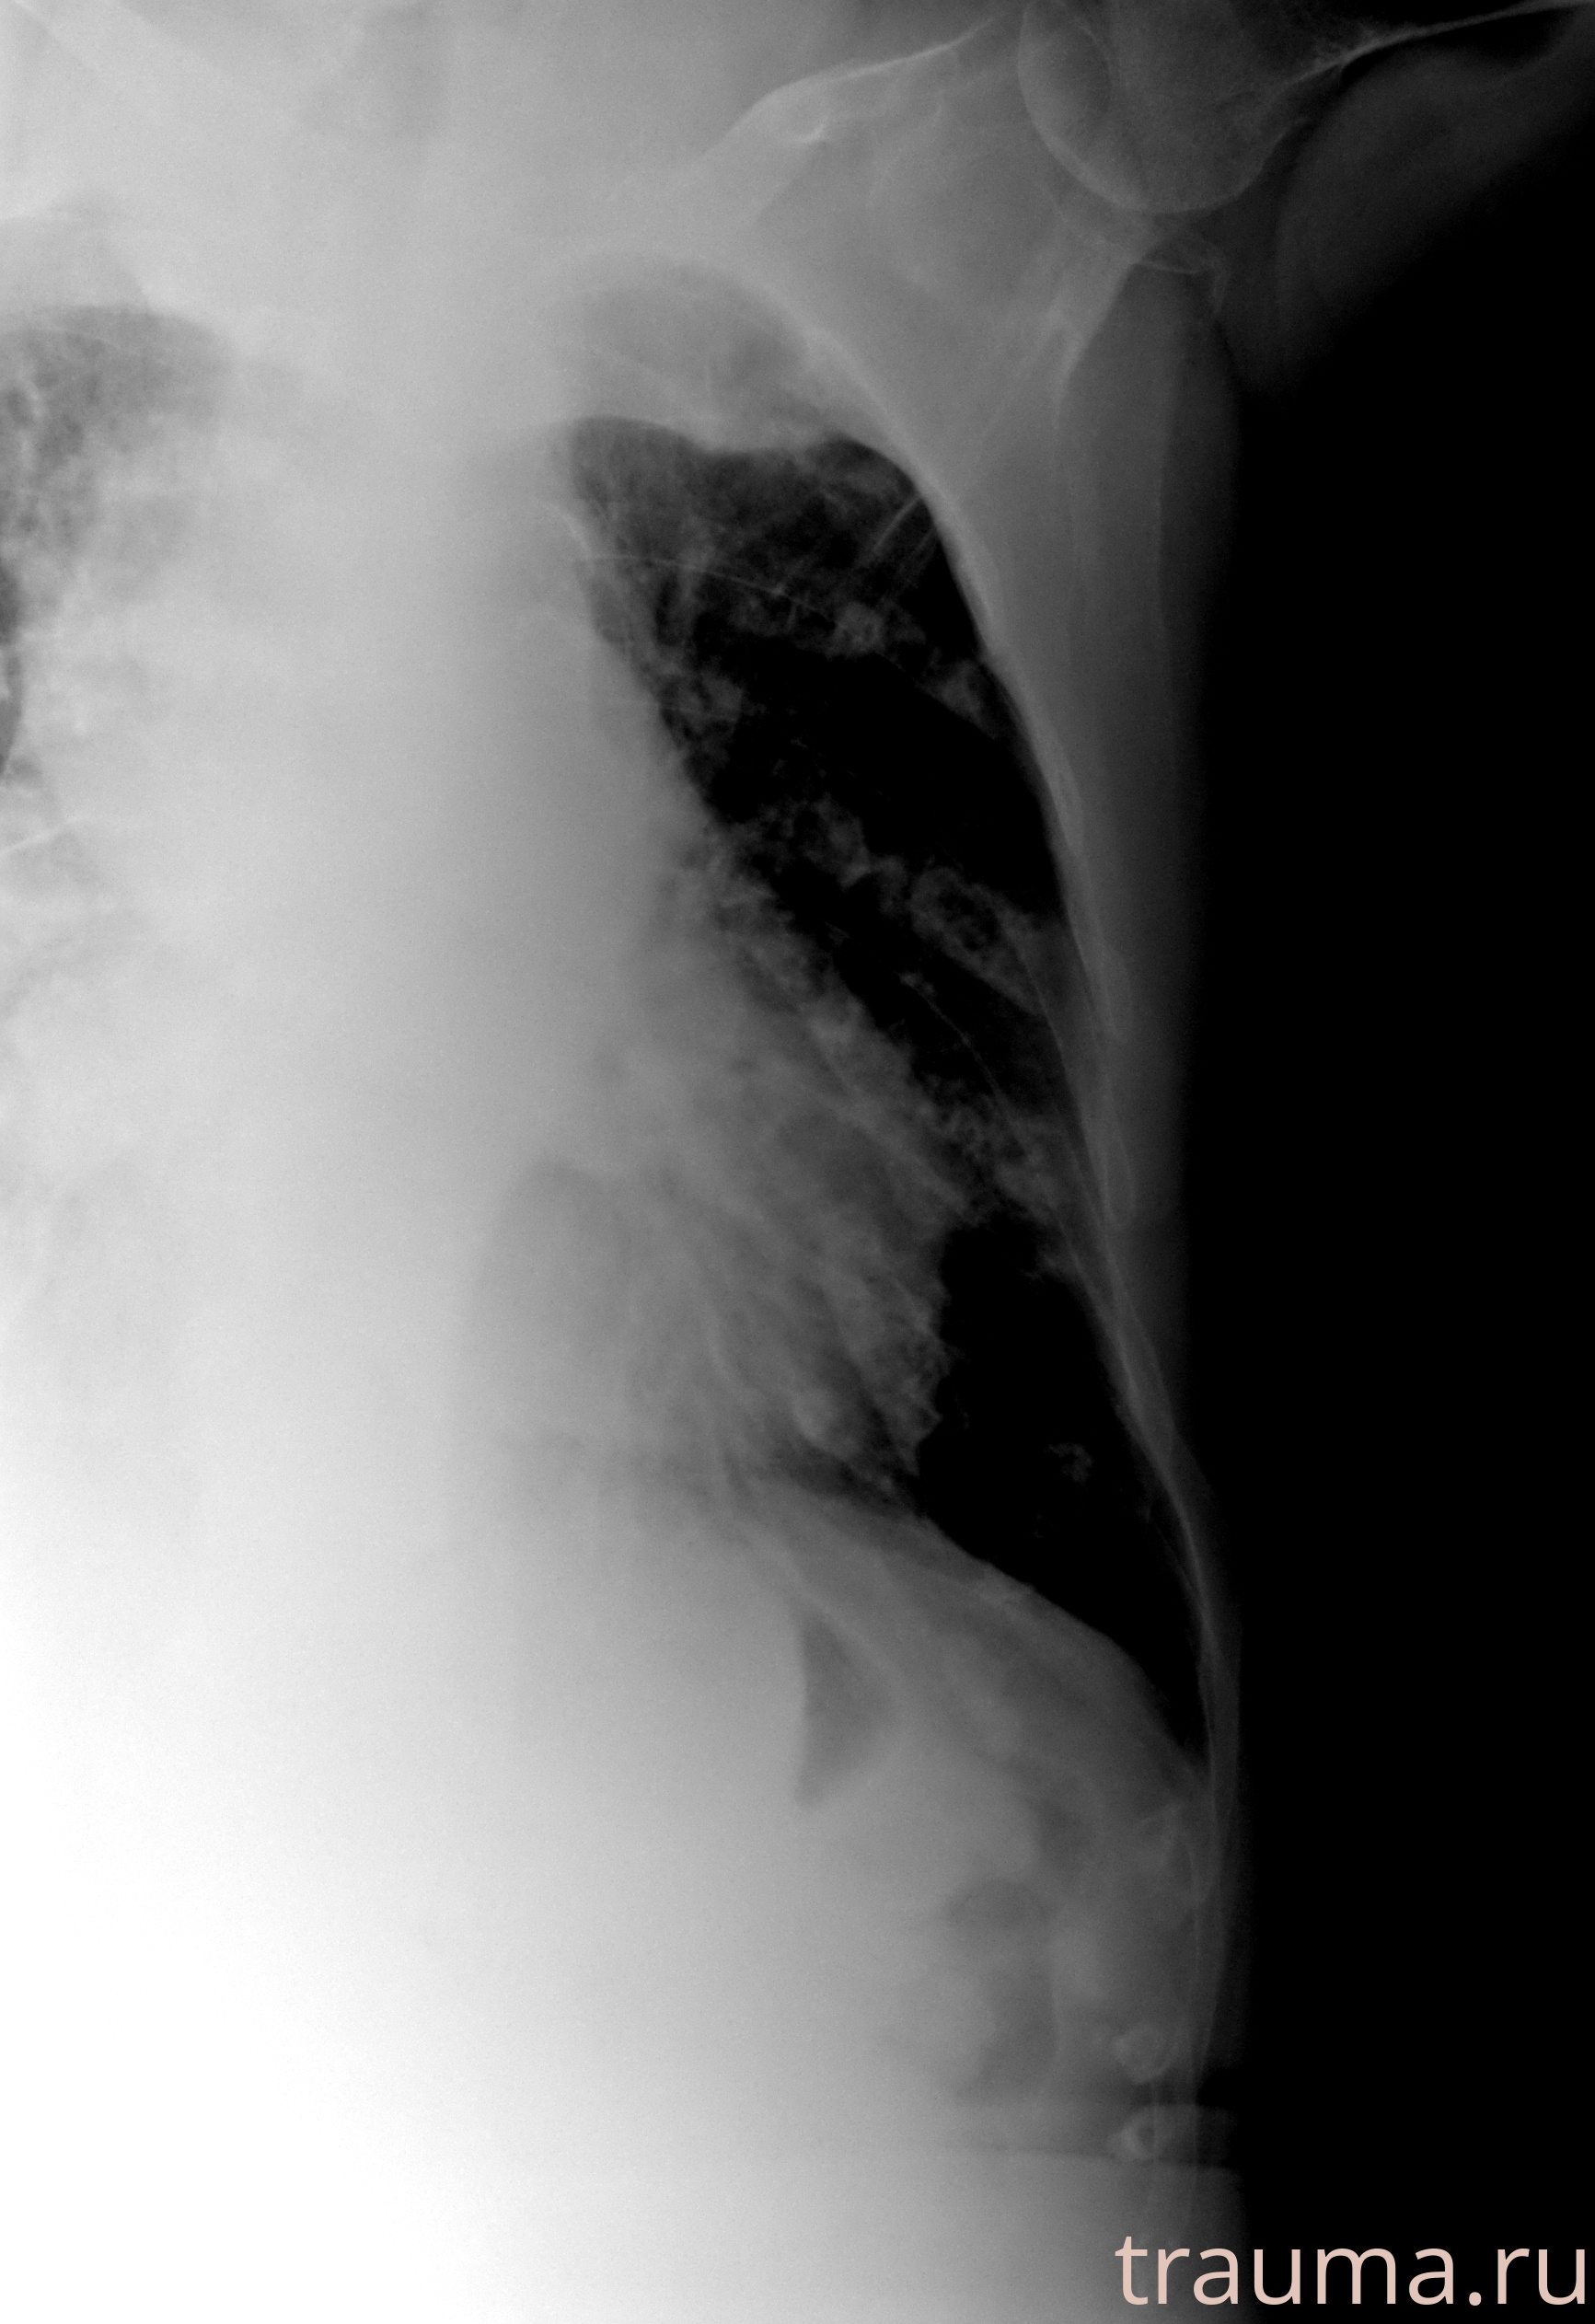

Рентген на дому: по вашему адресу приезжает врач-рентгенолог, травматолог-ортопед с мобильным рентгеновским аппаратом, проводит диагностику травмы или заболевания, делает необходимые рентгенограммы, дает рекомендации по дальнейшему лечению. Получить качественные снимки в домашних условиях возможно благодаря уникальной методике, разработанной МосРентген Центром для института  Склифосовского

при переломе шейки бедра и пневмонии от компании МосРентген Центр - партнера Института имени Склифосовского